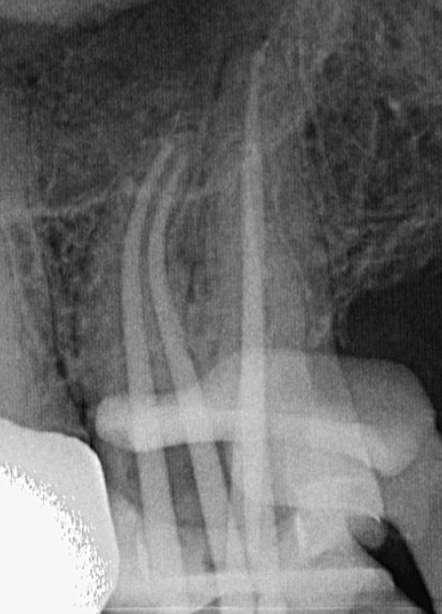

Die endodontische Behandlung fand in einer Sitzung statt. Nach Anästhesie und Anlegen des Kofferdams erfolgte die Entfernung der provisorischen Füllung und die initiale intrakoronale Diagnostik. Mittels Microopener konnte ein mesiobukkaler, mesiolingualer, distobukkaler und distolingualer Wurzelkanal sondiert werden. Die Ausarbeitung der primären Zugangskavität zur besseren Zugänglichkeit der Kanäle erfolgte mit Langschaftrosenbohrern. Anhand des präoperativen diagnostischen Röntgenbilds konnte die Länge der Wurzelkanäle vorläufig näherungsweise bestimmt werden. Die Kanäle wurden im weiteren Therapieverlauf kontinuierlich mit 6% NaOCl gespült. Nach Ausarbeitung der Zugangskavität folgte die koronale Erweiterung der Wurzelkanäle mit EdgeEndo X7 Feilen der Größe 17.06. Die elektrometrische Bestimmung der Kanallänge mithilfe eines Morita Root ZX Mini Apex Locators wurde mit C-Piloten der Größe 8-10 durchgeführt. Nach Festlegung der Arbeitslänge wurde der

Gleitpfad rotierend mit EdgeFile X7 der Größe 17.04 und 25.04 erweitert und final bis auf 30.04 aufbereitet (Abbildung 2).

Abbildung 1: Präoperative Diagnostische Aufnahme

Abbildung 2: Blick auf das mesiale Kanalsystem nach Präparation